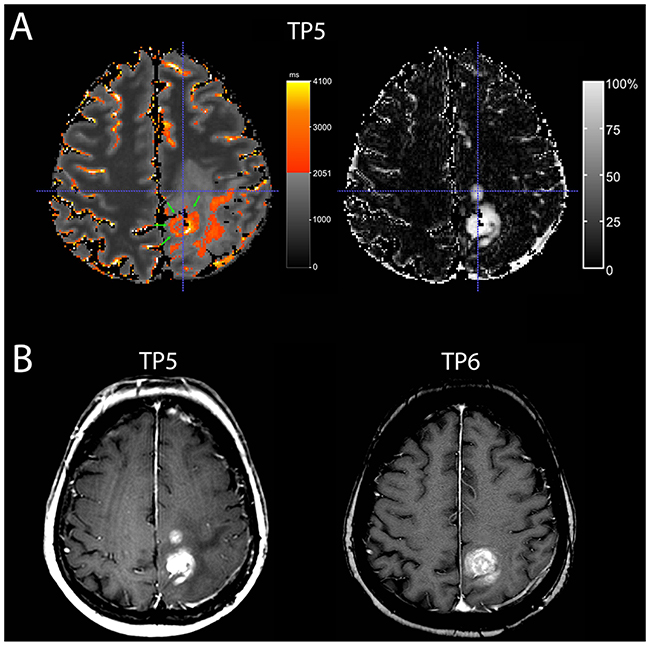

A moderate overlap was found at least one time-point in four patients (Table 1, patients 3,4,8,9). A predominantly moderate overlap, i.e. a moderate overlap at least 2 of 3 time-points, however, was only seen in two patients (Table 1, patients 3,9). As evidenced by the respective ΔqT1 maps (gold standard), those two patients had mainly necrotic tumors at the time of progression. In one patient (Table 1, patient 9), the contrast-enhancing area, which did not overlap with the qT1-prolonged area, regressed at the next MRI timepoint, whereas the overlapping contrast-enhancing tumor progressed (Figure 3).

Figure 3: A patient with moderate overlap (patient 9). A Quantitative map with a subtraction map qT1 at time-point TP 5) (A) and conventional MRI at TP 5 and TP 6 (B) of a 70-year-old woman with recurrent GBM. At TP 5, the quantitative map (A, on the left-hand side) shows pre-GBCA qT1 area with >2051 ms (red to yellow, green arrows) with a good overlap of the dorsal contrast-enhancing tumor seen on the subtraction map ΔT1 (A, on the right-hand side), but the second smaller contrast-enhancing tumor area (crosshair) is missing on the color map. This contrast-enhancing area without overlap (crosshair) regressed in the next conventional MRI (TP 6) (B), whereas the contrast-enhancing tumor with overlap progressed. Also, note additional area of T1-prolongation outside the contrast-enhancing tumor.